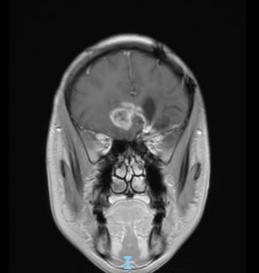

44歲的郭先生(化姓)為膠質(zhì)瘤復(fù)發(fā)患者,復(fù)查發(fā)現(xiàn)顱內(nèi)占位進(jìn)行性進(jìn)展1周,MRI檢查提示瘤體已累積到胼胝體,且瘤體位置較深,手術(shù)難度極高。面對這一挑戰(zhàn),王虎教授團(tuán)隊(duì)決定采用多種先進(jìn)技術(shù)輔助手術(shù),其中最為引人注目的就是首次引入的細(xì)胞級顯微鏡EndoSCell?。該設(shè)備是目前全球唯一實(shí)時(shí)在體細(xì)胞級顯影的儀器,可以輔助醫(yī)生從細(xì)胞層面區(qū)分腫瘤組織與正常組織,從而做到細(xì)胞級精準(zhǔn)切除。

患者術(shù)前核磁影像